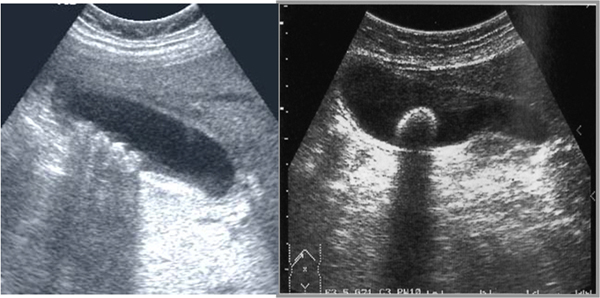

초음파검사로 확인…내시경 등 치료법 다양

담즙은 간세포에서 만들어져 담낭(쓸개)내에서 일시적으로 머물다가 음식물을 섭취하면 담낭이 수축하면서 담관을 통해 십이지장으로 배출, 소화작용을 돕게 된다. 담석증은 담즙이 흐르는 길에 돌이 형성된 것을 말한다. 담석이 생길 수 있는 부위에 따라 간내 담관석, 간외 담관석, 담낭 담석 등으로 구분한다. 이 가운데 담낭 담석의 빈도가 제일 높다. 담석을 종류별로 살펴보면 콜레스테롤 담석, 색소성 담석, 혼합형으로 나눌 수 있다.

치료방법은 담석의 위치, 합병증의 동반유무에 따라 다양하다. 일반적으로 담낭 내에 있는 담낭결석은 결석에 의한 증상이 없으면 경과 관찰한다. 무증상 담석증은 대부분 증상 발현율이 낮고 합병증의 발생 빈도가 낮아 몇가지 예외 경우를 제외하고는 예방적 담낭 절제술을 할 필요가 없다. 하지만 1㎝ 이상의 담낭용종이 동반된 경우 등 담낭암과 감별이 어렵거나 발생 위험이 높다고 여겨지는 경우 수술을 고려할 수 있다. 담관결석의 경우, 간외 담관에 있는 담석은 대부분 내시경적 역행성 담도조영술(ERCP)을 통해 제거한다.